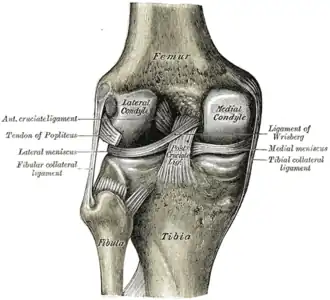

Anterior view of knee.